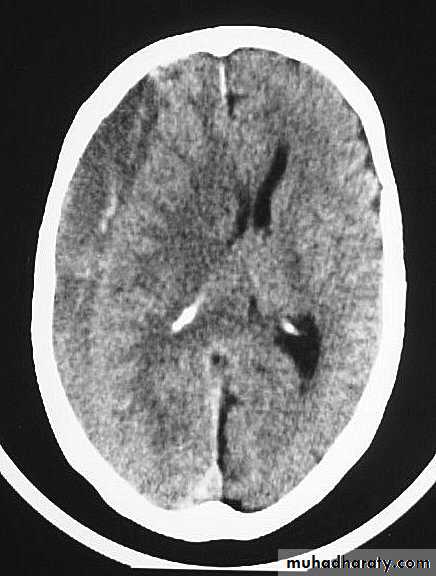

CT scan: the acute clotted blood is initially appears white (hyperdence), but as it liquefies, it slowly becomes black (hypodense).

They should be drained if they continue to enlarge.

They are evacuated by drilling burrholes over the collection and washing it out with warmed saline.

Chronic Subdural Haematoma